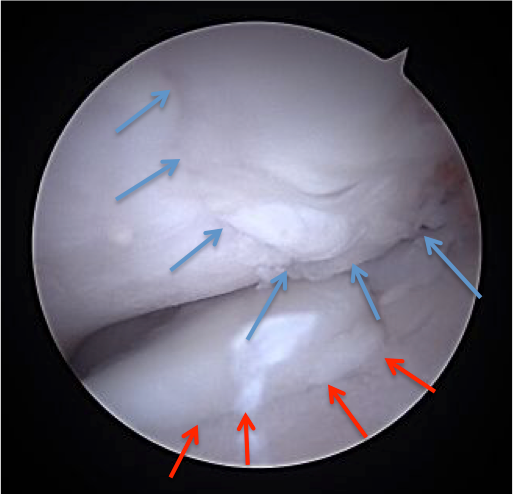

Arthroscopie d'un coude montrant une lésion d'ostéochondrose (flèches bleues) et une lésion de fragmentation du processus coronoide médial (flèches rouges)